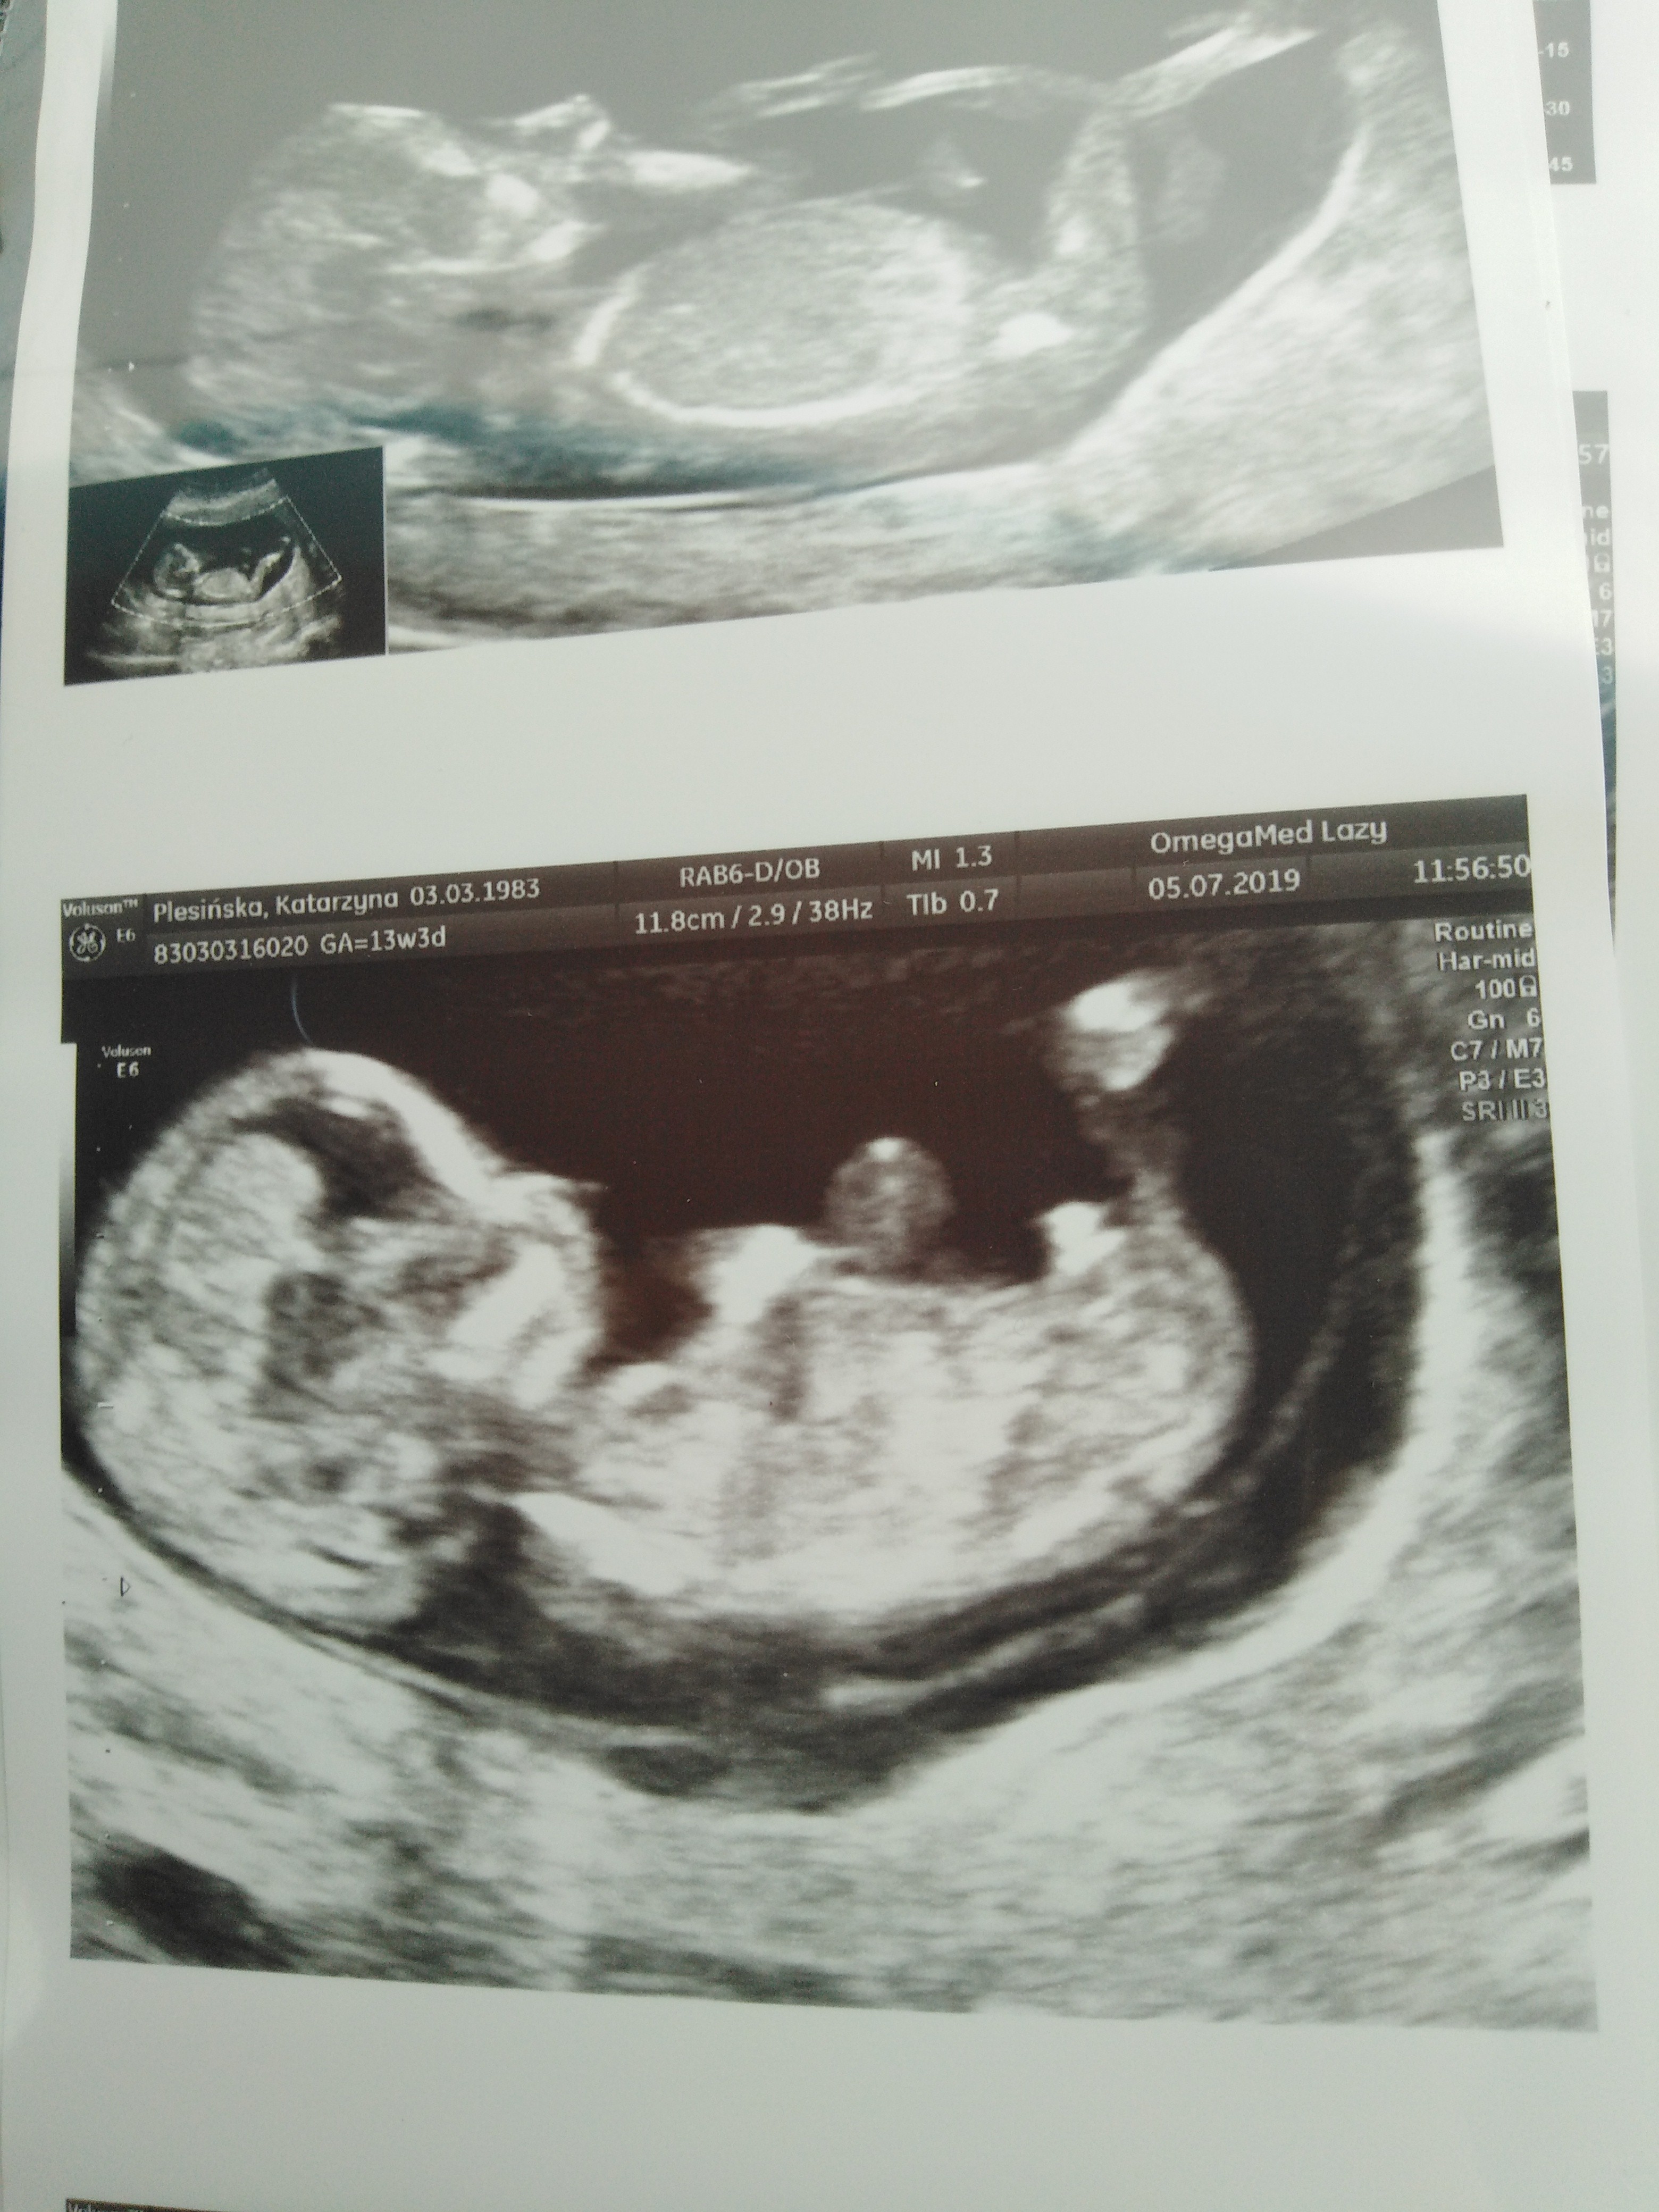

Cześć. Mam na imię Lucyna, mam 36 lat i jestem w 11tc.Termin mam na 25.01.2020.To moja 4 ciąża.